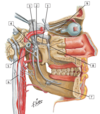

15

Q

1

A

1 - facial artery and vein

16

Q

2

A

2 - retromandibular vein

17

Q

3

A

3 - external jugular vein

18

Q

4

A

4 - anterior jugular vein

19

Q

5

A

5 - common carotid artery

20

Q

6

A

6 - internal jugular vein

21

Q

7

A

7 - superior thyroid artery and vein

22

Q

8

A

8 - external carotid artery

23

Q

1

A

1 - vertebral artery

24

Q

2

A

2 - costocervical trunk

25

#3

#3 - supreme intercostal artery

26

#4

#4 - internal thoracic artery

27

#5

#5 - suprascapular artery

28

#6

#6 - thyrocervical trunk

29

#7

#7 - common carotid artery

30

#8

#8 - transverse cervical artery

30

#9

#1 - inferior thyroid artery

31